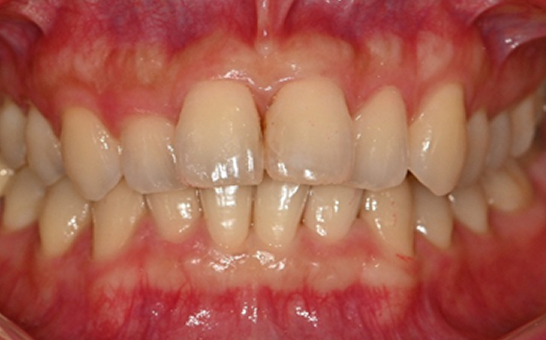

인비절라인 퍼스트(Invisalign First)는 어린이와

성장기 청소년을 위한 투명 교정 장치로, 치아와 턱뼈가

성장하는 과정에 맞춰 설계된 교정 시스템입니다.

해당하는 증상이 있다면 전문의와 상담 후 조기 교정 시

성장기 어린이에게 교합이 틀어지는것을 미리 예방 할 수 있습니다.

※ 바른선택치과의원은 의료법을 준수하며 위 케이스는 실제 내원 환자분의 동의하에 공개된 사진과 동일한 환자분께 같은 조건에서 촬영한 사진을 활용했습니다.

개인에 따라 진료 및 치료 방법이 다르게 적용할 수 있으며, 효과와 부작용이 개인마다 다르게 나타날 수 있는 점을 안내해 드리며, 진료 전 전문의료진과 충분한 상담을 권해드립니다.